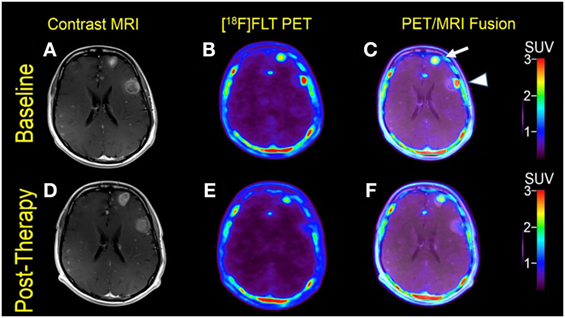

Multiple cerebral lesions demonstrated variable mild to intense FLT uptake at baseline, followed by a marked reduction in FLT uptake at 3 weeks of therapy; however, most lesions still showed mild FLT uptake higher than that of the pons background suggestive of partial treatment response or possibly proliferation of inflammatory cells at the sites of tumor response (Table 1). The six measured lesions showed −68% (range −38 to −77%) median reduction in proliferative activity at 1-month follow-up; there was no new FLT avid cerebral lesion. The median SUVR was 8.3 (range 6.4–11.9) at baseline and 2.7 (range 2.4–4.4) at follow-up scan. Compared to PET findings, the size reduction on MRI was lower with a median of −23% (range −4 to −55%), and there was no evidence of new metastasis (Figure 1). A standard-of-care clinical brain MRI scan obtained 8 weeks later showed a further reduction in the size of MBM.

FIGURE 1

Figure 1. Case #1. Baseline magnetic resonance imaging (MRI) (A), fluorothymidine (FLT)–positron-emission tomography (PET) (B), and fused PET/MRI (C); follow-up MRI (D), FLT–PET (E), and fused PET/MRI (F) at 3 weeks. Bilateral supratentorial brain lesions of greater than 1 cm demonstrate variable mild to intense FLT avidity. They showed a greater proliferative reduction compared with the size reduction at 1-month follow-up. Gadolinium-enhanced T1-weighted spin echo with TR 708 ms, TE 8.4 ms, and 90° flip angle, 5 mm slice thickness.